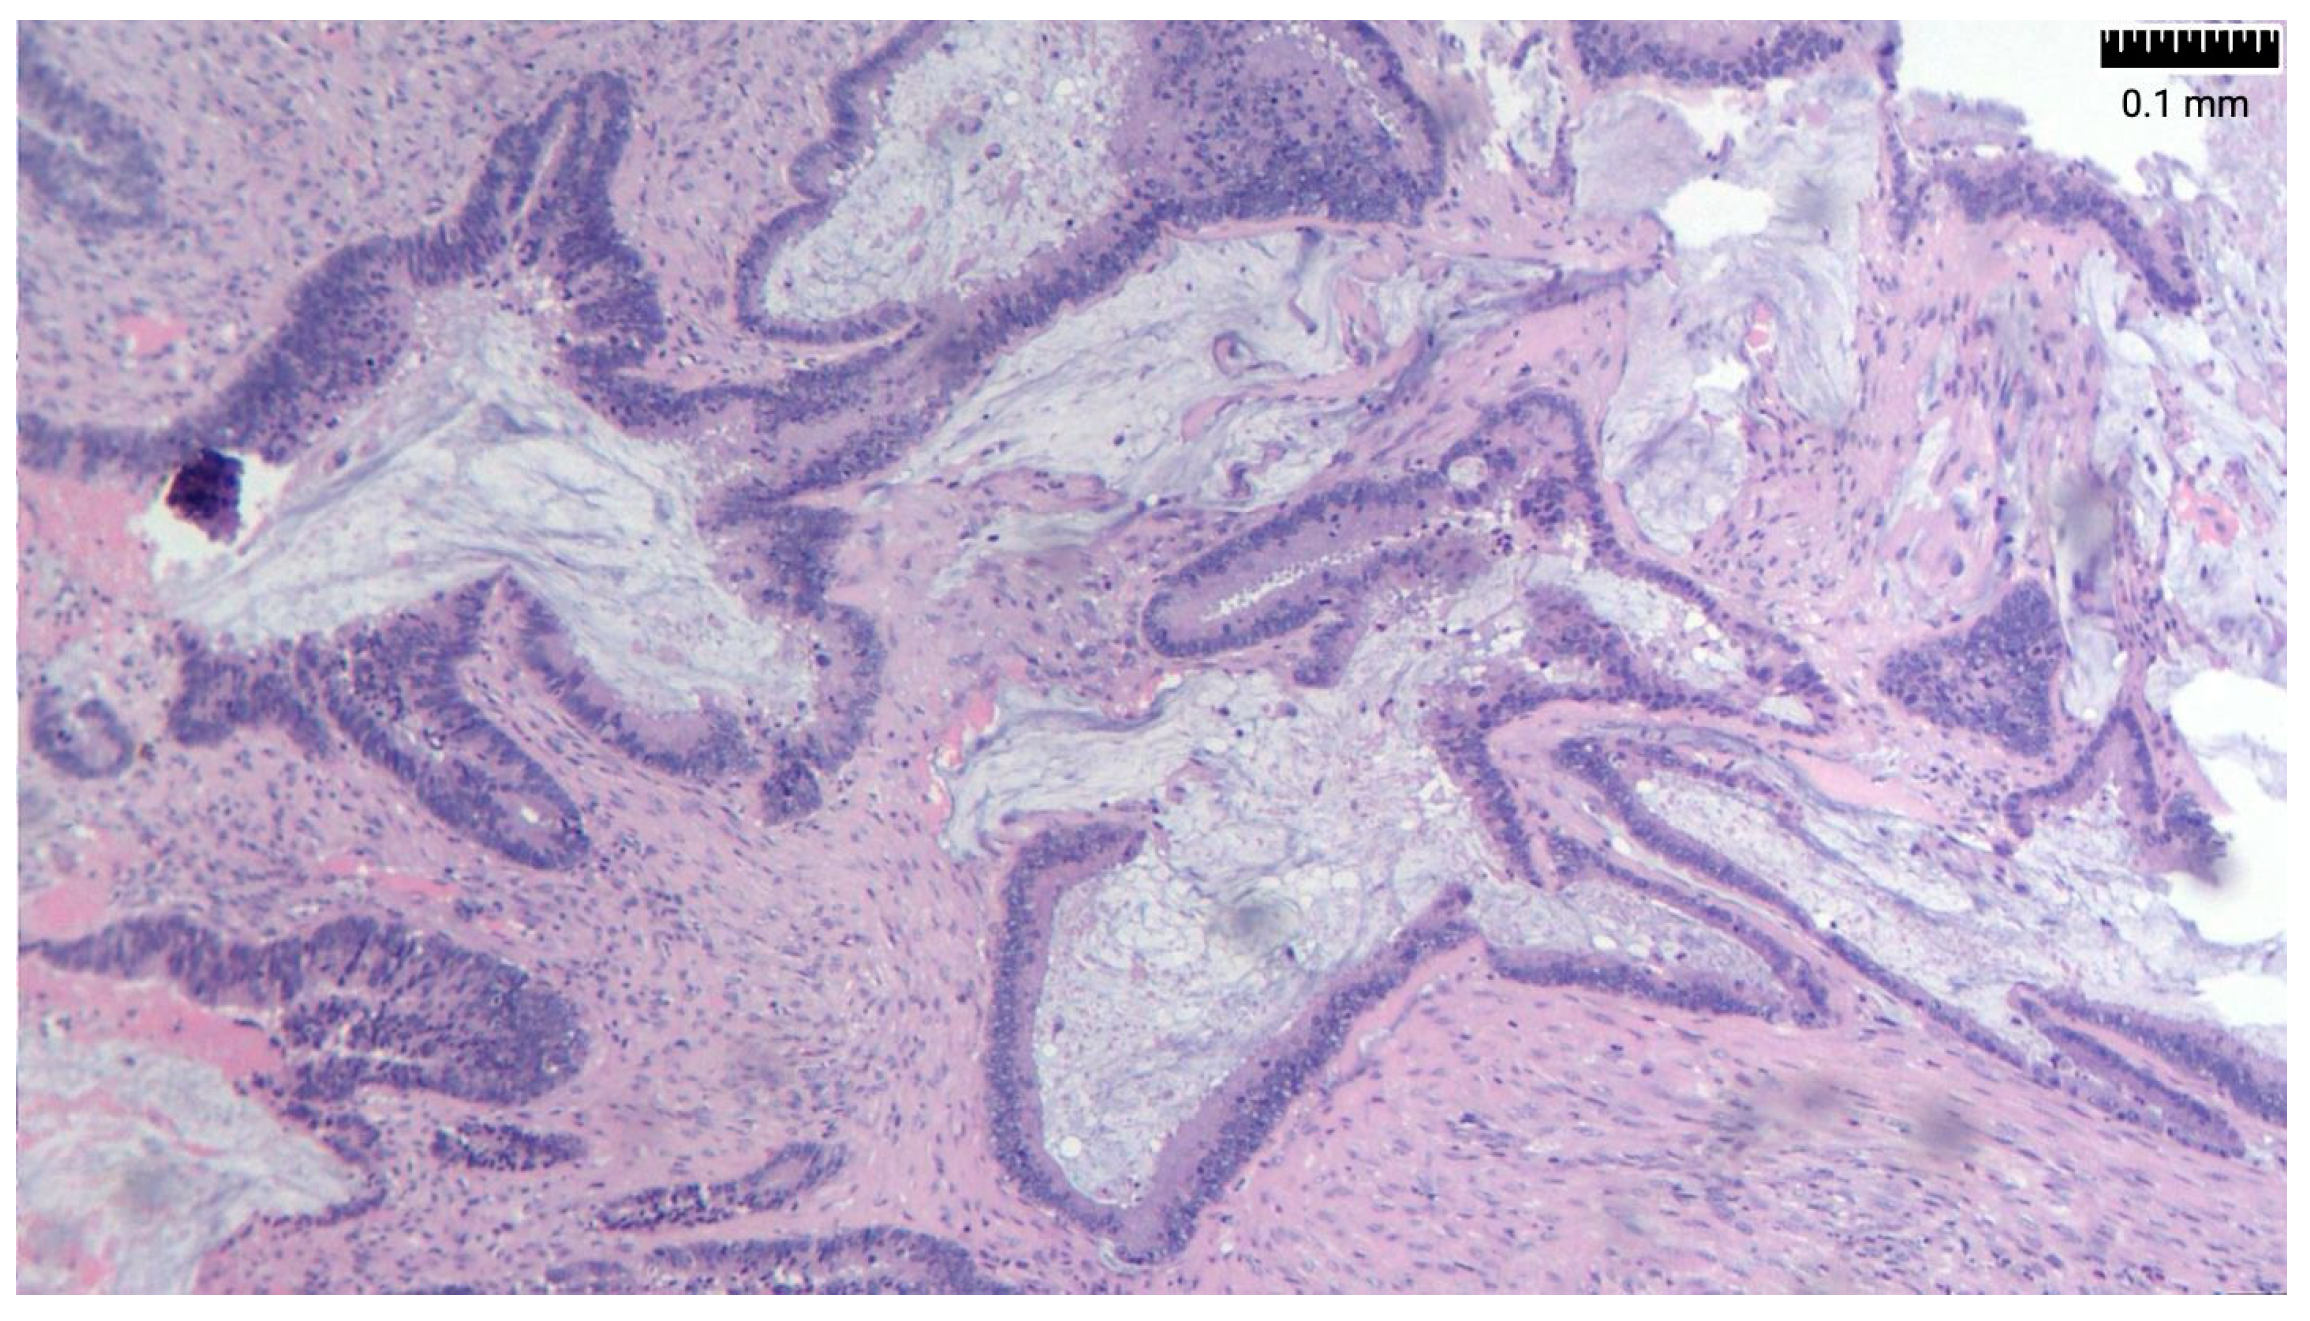

- Acellular mucin—mucin within the peritoneal cavity without neoplastic epithelial cells.

- Low-grade mucinous carcinoma peritonei (synonymous with DPAM)—mucin with low cellularity (less than 10%) and without infiltrative growth.

- High-grade mucinous carcinoma peritonei (synonymous with PMCA)—mucin with high cellularity, moderate/severe cytological atypia, numerous mitoses, and a cribriform growth pattern. Infiltrative invasion of the underlying organs is often present.

- High-grade mucinous carcinoma peritonei with signet ring cell is classified separately because of its worse prognosis.